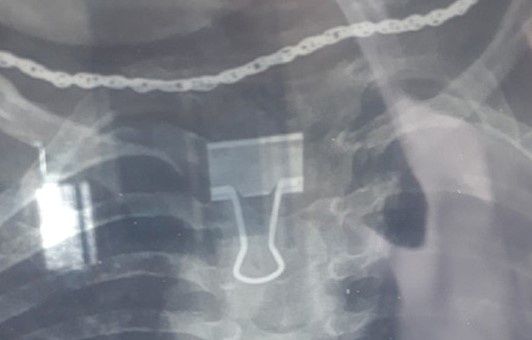

Chụp X-quang, bác sĩ phát hiện bệnh nhi 2 tuổi ở Thanh Hóa bị mắc một chiếc kẹp giấy trong thực quản.